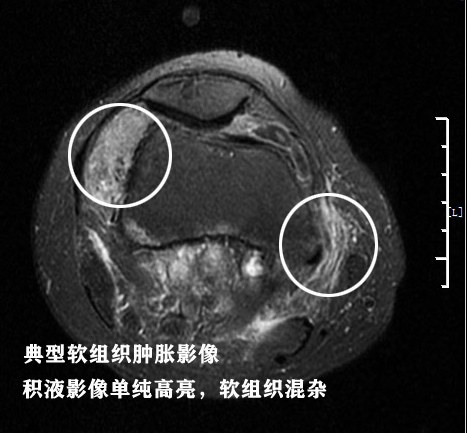

第四,周围软组织肿胀。软组织肿胀的影像主要是T2像更加明确,肿胀的影像和积液影像差别不大,但是积液的影像是单纯的一片高亮影像,而软组织肿胀是混杂的、不均匀的影像。